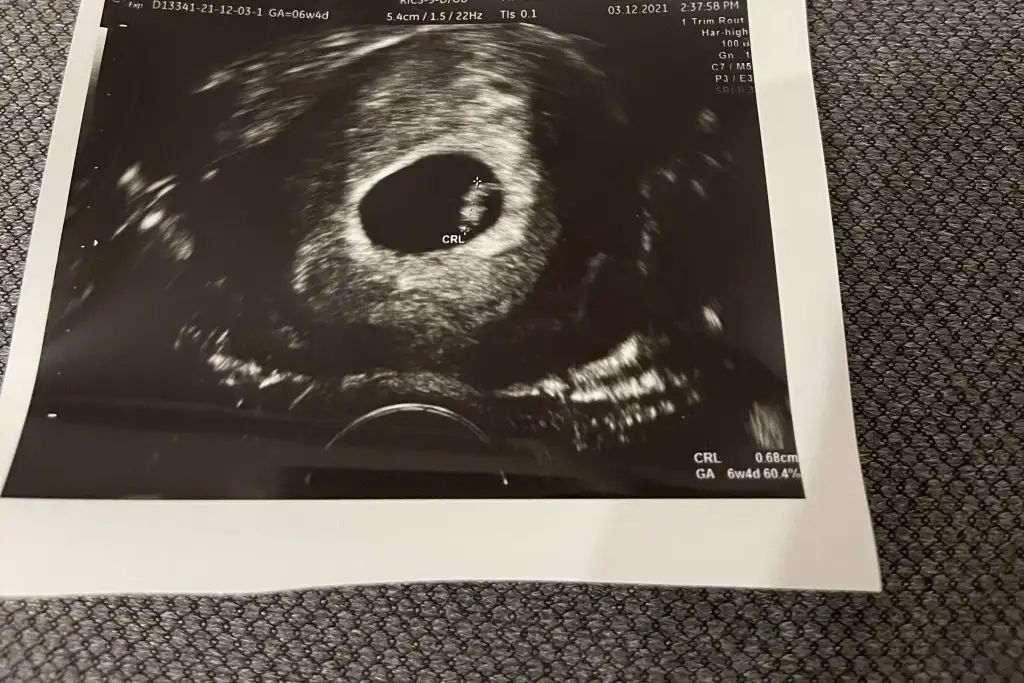

Kızlar bu ultrason kağıdından cinsiyet tahmin etme diye bir şey varmış. Duydunuz mu hiç böyle bir şey?

Canım bebek kesenin solunda ise erkek sağında ise kızmış fasülye gibi ise erkek yuvarlak ise kızmış☺️ At ultrason fotoğrafını yorumlayalım😂

Ramzi teorisini kendiniz uygulayabilirsiniz. 6-7 . haftalara ait ultrason görüntünüz eliniz de varsa inceleyin. Bebek sağ tarafta ya da sağ tarafa daha yakınsa kız , Eğer bebek sol tarafta ya da sol tarafa yakınsa cinsiyeti erkektir.

Gebeliğin yine 6-7. haftalarında ki vajinal ultrason ile bebeğin konumuna göre cinsiyet tahmini yapılıyor. Bebek sağda ise erkek , sol yada sol tarafa yakın sa bebek kız demekmiş.

Burda yazılana göre seninki de benimki de kız 😂 vajinalde seninki baya yuvarlak birde kese bak bende vajinal görüntümü atıyorum. Şimdi

Eğer o siyah kısım rahim ise içindeki beyaz şey bebek ise ikimizin de erkek oluyor. Çünkü sağ tarafta. 🙄 ben mi yanlış anladım bilmiyorum 😂